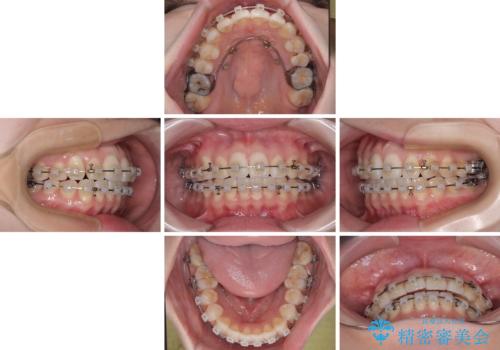

補助装置を用いて上顎臼歯を後方移動させ、歯列を整えながら前歯部の接触を図ることとしました。

舌の突出癖改善のためのトレーニングを指導しながら、ワイヤー装置にて矯正治療を行うこととしました。